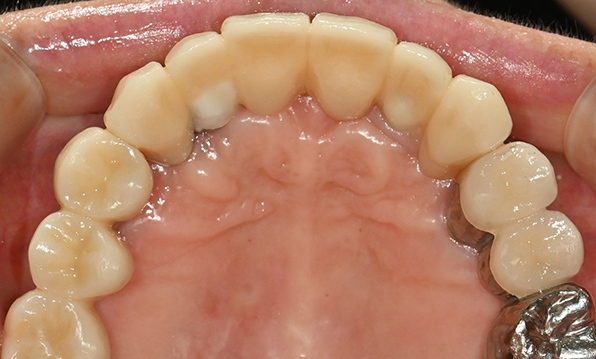

| Before | After |